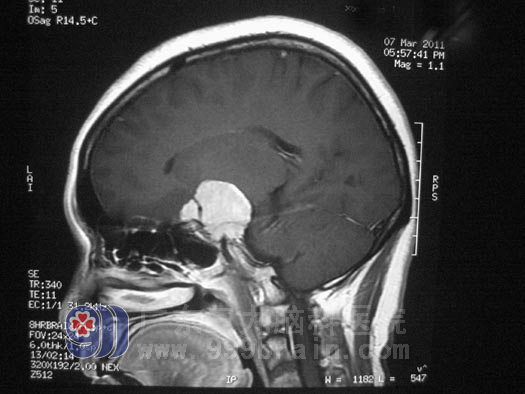

神经外五科鲁明主任分析后指出:许女士右眼视力下降与右侧鞍区占位有关,从头颅MRI上看,右侧鞍区占位内有许多血管通过,右侧颈内动脉被肿瘤包裹,有受压变细,术中分离肿瘤可能损伤颈内动脉。经过慎重考虑决定先行造影栓塞后再行手术治疗,避免术中大量出血,减少手术的风险性。3月20日,许女士在介入室行肿瘤部分供血血管栓塞术。3月22日,由鲁明主任主刀,在全麻下行“右侧蝶骨嵴脑膜瘤切除术”, 术中见肿瘤位于右侧中颅窝底,其基底部位于右侧蝶骨嵴、前床突位置,包绕右侧颈内动脉并延伸至对侧鞍旁,右侧视神经被肿瘤包绕并向上抬起,右侧动眼神经、外展神经被肿瘤压迫位于肿瘤外侧,肿瘤质地较软,血供丰富。显微镜下小心分离,将肿瘤分块全切,椎动脉及其分支位于肿瘤后下方,过程中右侧颈内动脉及其分支、椎动脉及其分支、双侧视神经、外展神经及动眼神经保护完好,手术成功完成。术后患者病理结果为:(右侧蝶骨嵴)脑膜皮细胞型脑膜瘤,WHOI级。

▲手术前影像(红圈内为穿过肿瘤的动脉血管)